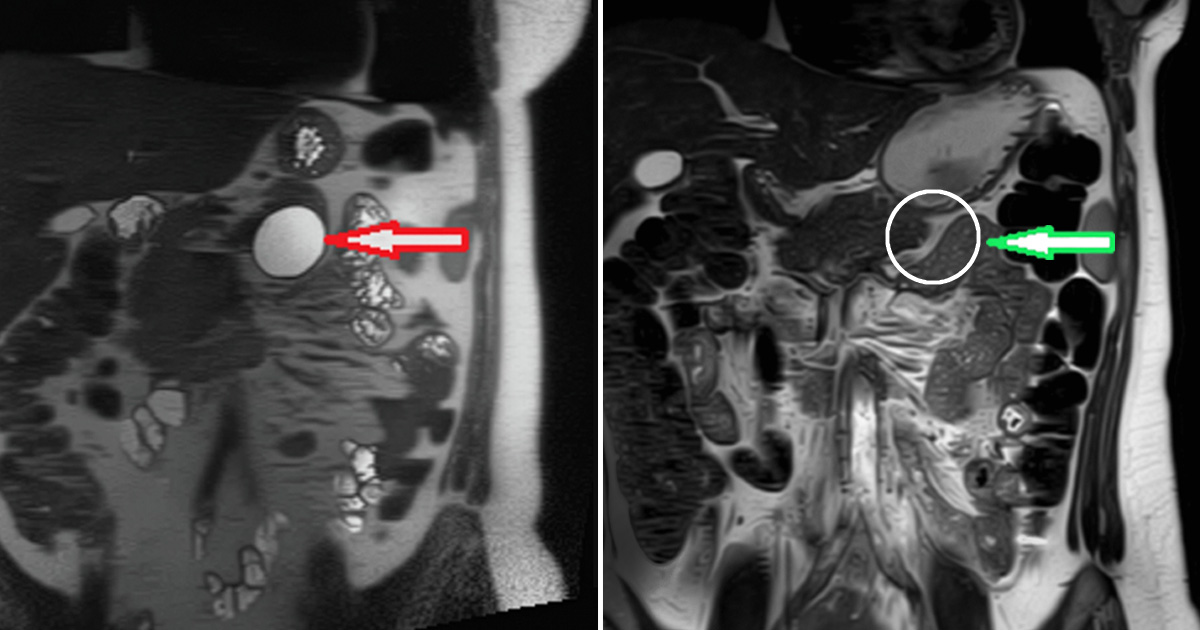

Pancreatic cancer is one of the deadliest forms of cancer. Penn State’s new procedure gives patients peace of mind and a second chance at life.